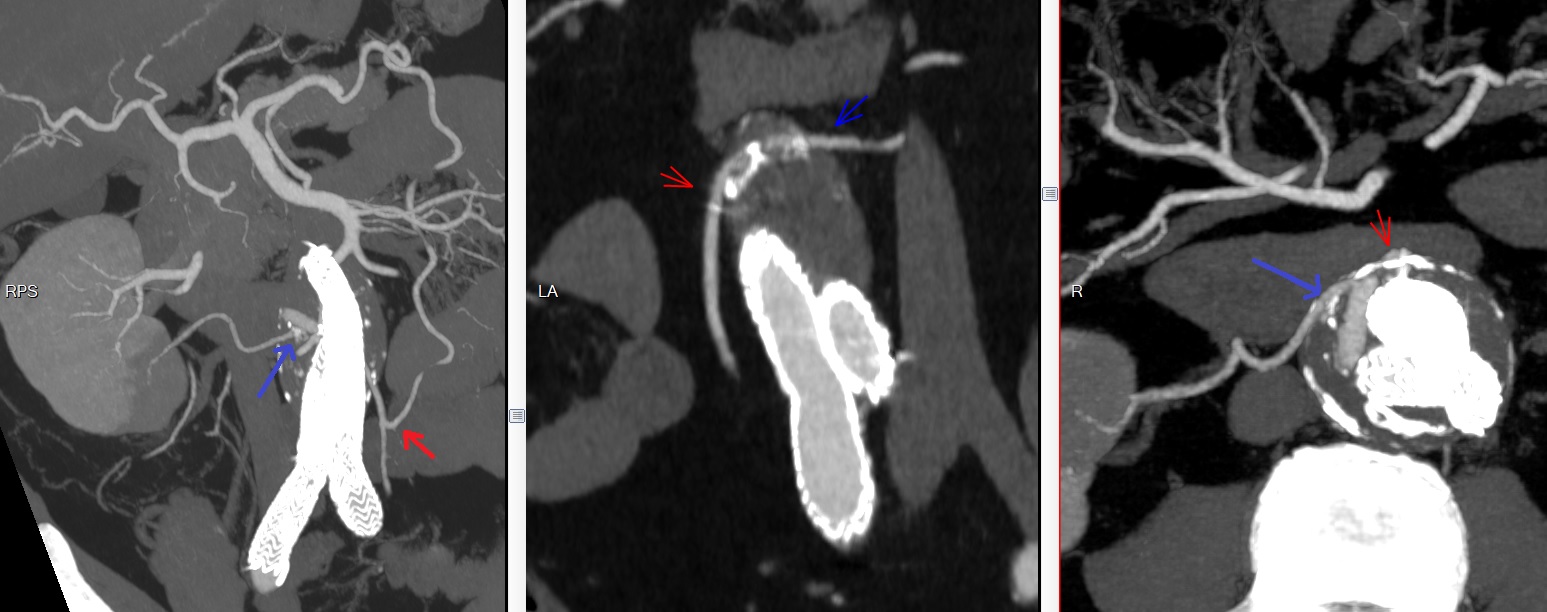

Type 3

IIIc Deconnexion de stent

IIIc Sortant du stent rénal droit